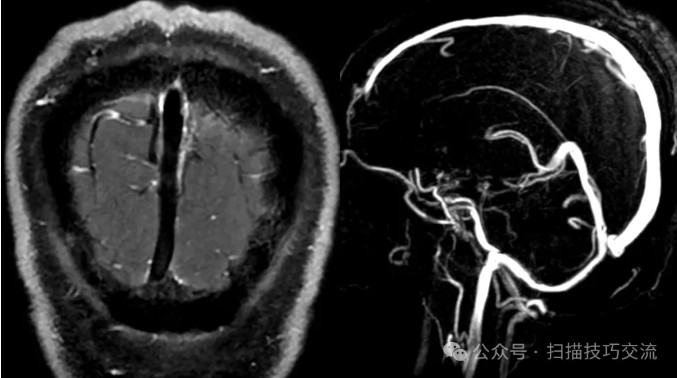

静脉有扩张,无血栓。

来都来了,再加个3D MRM看一下,